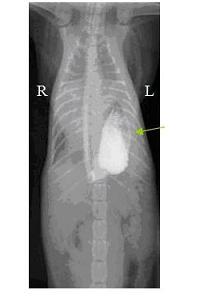

המקרה של צ'פאי